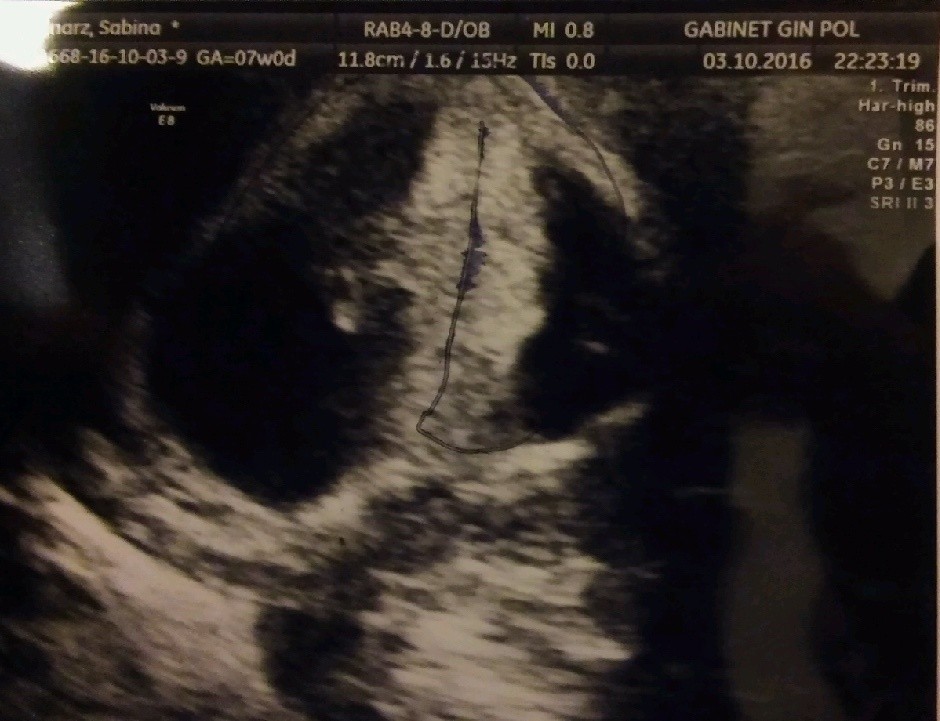

A to moje kropkiBliźnięta dwukosmówkowe, według OM 7 tyg 2 dni, według USG 6 tyg 5 dni